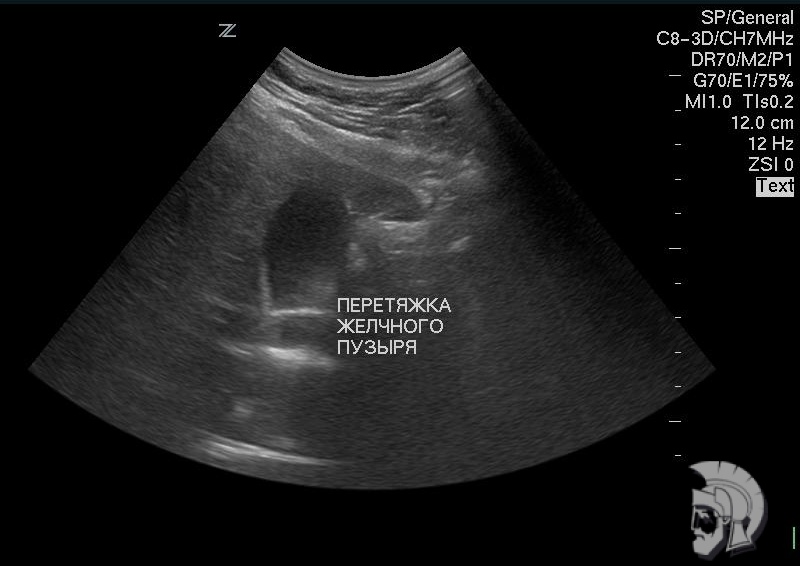

| Фото желчного пузыря. Желчный пузырь с перетяжкой у мужчины 28 лет. Желчный пузырь определяется в виде «тёмного» образования S - образной формы. Перетяжка определяется на границе средней и нижней третей желчного пузыря в виде выступающей «светлой» полоски |